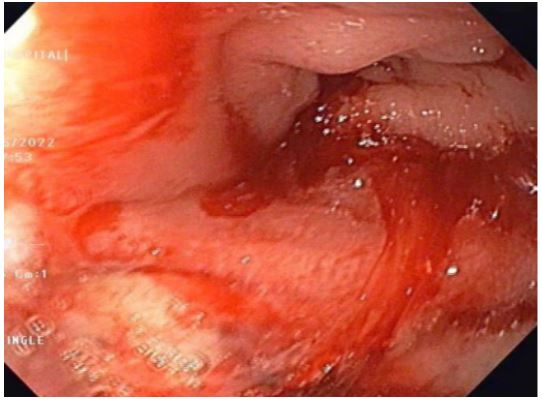

A 59-year-old man has complained of pus and mucus discharge from the anal region, as well as intermittent fever episodes, for the past two years. Three years ago, he developed symptoms of per rectal bleeding and was diagnosed with Carcinoma rectum, for which he received three cycles of neoadjuvant radiotherapy followed by laparoscopic anterior resection with a defuncting descending colostomy. He was discharged on post-operative day 8, with no issues reported. Adjuvant Chemotherapy was administered in 13 cycles. After 6 months of surgery, a CT abdomen was performed, which showed post-op changes in the pelvis with Pelvic peritoneal fat stranding and widening of the presacral space. He was having repeated episodes of fever with chills and pus discharge per anus that were resolved with IV antibiotics. After 6 months, an MRI of the pelvis revealed a significant collection of size 9.1 x 5.2 x 8.8 cm with air loculi at the presacral area-most likely a controlled leak (Figure 2). The conservative approach was continued for another six weeks, during which an intermittent fever with mucus and pus discharge from the anal region persisted. A colonoscopy was performed, which showed the cavity and confirmed the findings (Figure 4). Endovac sponges were sutured to RT and placed directly into the cavity with the help of a colonoscope after debriding and irrigating the cavity. After applying post-E-VAC therapy, the patient improved and had no fever after 48 hours. The procedure was repeated on an OPD basis four more times, with the endovac in place for five days each. At each session of endoscopy, there was a reduction in the size of the sponge used and considerable improvement in terms of the size of the cavity and the amount of slough (Figure 5). The cavity completely healed 10 weeks after E-VAC therapy, and the patient has been asymptomatic for the past 4 months. A CT scan showed complete resolution of the leak.

Figure 4: Colonoscopy showing post operative leak after anterior resection of ca rectum and placement of EVAC.

Figure 5: Healing of rectal cavity after E- Vac.